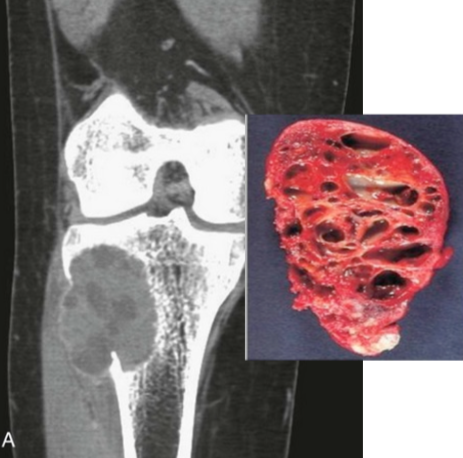

Aneurysmal bone cyst